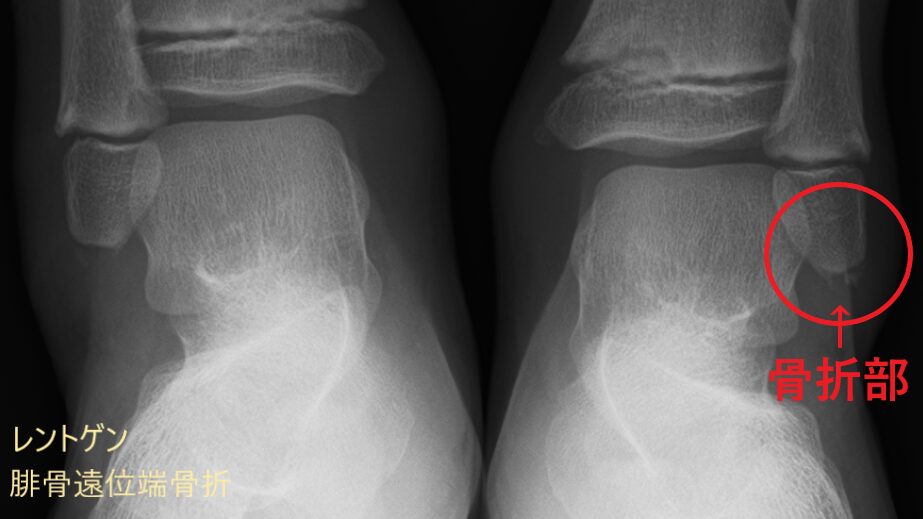

レントゲン画像には映りにくい筋肉や腱、靭帯などの状態に加え、骨の様子もあわせて確認できます。